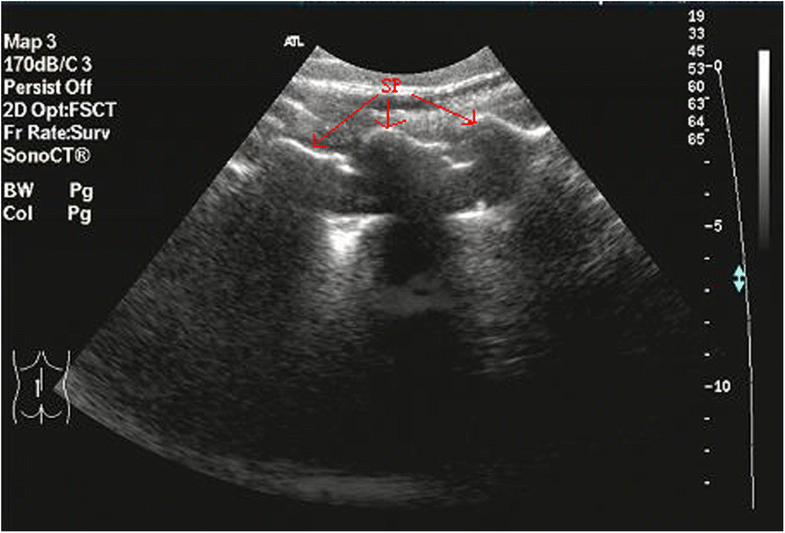

Ultrasound image showing sagittal plane of the facet joint. Download Facet Joint Ultrasound Web facet joints are the small joints between the bones (vertebrae) in your back or neck. Web cervical facet joints are a common cause of chronic neck pain. Arthritis or wear in these joints may cause. Web facet joint neoplasms like osteoid osteoma, plasmacytoma, tenosynovial giant cell. Radiofrequency neurotomy is a validated treatment technique for cervical. Web this paper aims. Facet Joint Ultrasound.

UltrasoundGuided Intervention in Cervical Spine